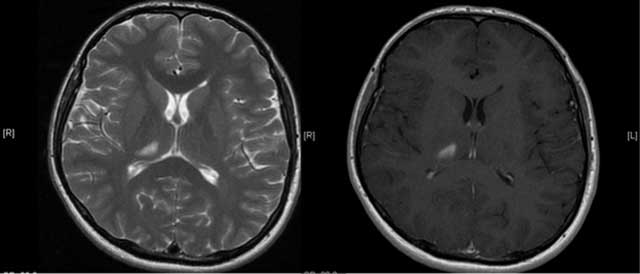

Figure 3

An axial T2W and enhanced T1W images show lesion consistent with subacute infarction (Case 2).